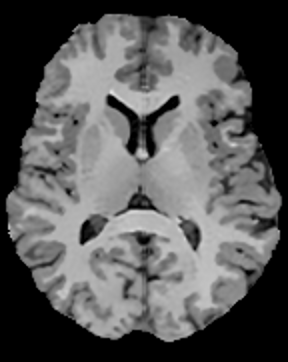

In this subsection, the MRI images from the built-in MRI dataset available in the MATLAB® toolbox have been used as test subjects. Specifically, the denosing algorithms have been tested using the axial slices number 4, 7 and 16 (shown in Figures 5, 5 and 5, respectively), which represent a spectrum of different cerebral structures. For quantitative comparison, simulated data have been obtained by subjecting the original test images to various levels of Rician noise.

Refer to caption

Figure 5: (a) Test slice #4, (b) Test slice #7 and (c) Test slice #16 of the MATLAB® MRI database.